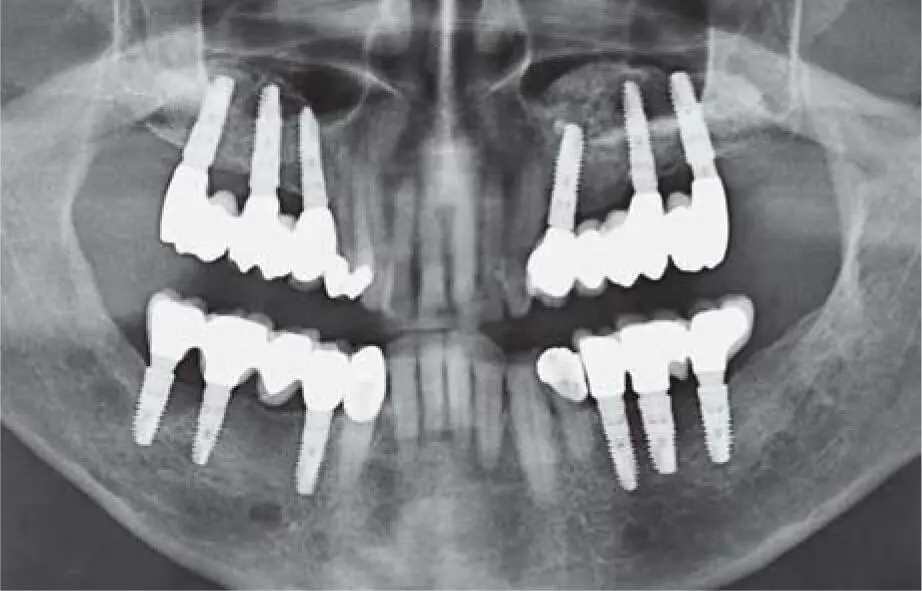

Fig 2-25cTwo donor sites in the retromolar area of the right and left mandible for multiple augmentation areas in the maxilla and mandible.

Fig 2-25dRecall radiograph 2 years postoperatively with implants that show good osseointegration.

Fig 2-25eControl radiograph 12 years postoperatively.